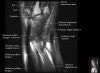

- Axial section

Axial T1 evaluates the tendons of the wrist and carpal tunnel, including the flexor retinaculum.